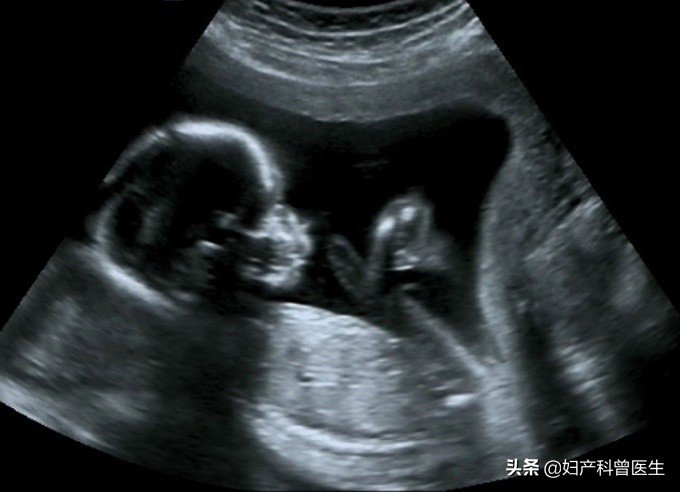

B超显影的胎儿图

第三次:孕20-24周

就是通常大家说的四维检查,孕中期系统筛查,是排查胎儿畸形的最佳时期。这个时期可以观察到胎儿头部、肢体和各脏器大体结构,排查六大严重致死性畸形,对胎儿面部、神经系统、消化系统、泌尿系统以及其它系统的常见结构畸形做出筛查判断。这次检查也是5个阶段中最重要的一次超声检查,十分有必要做。